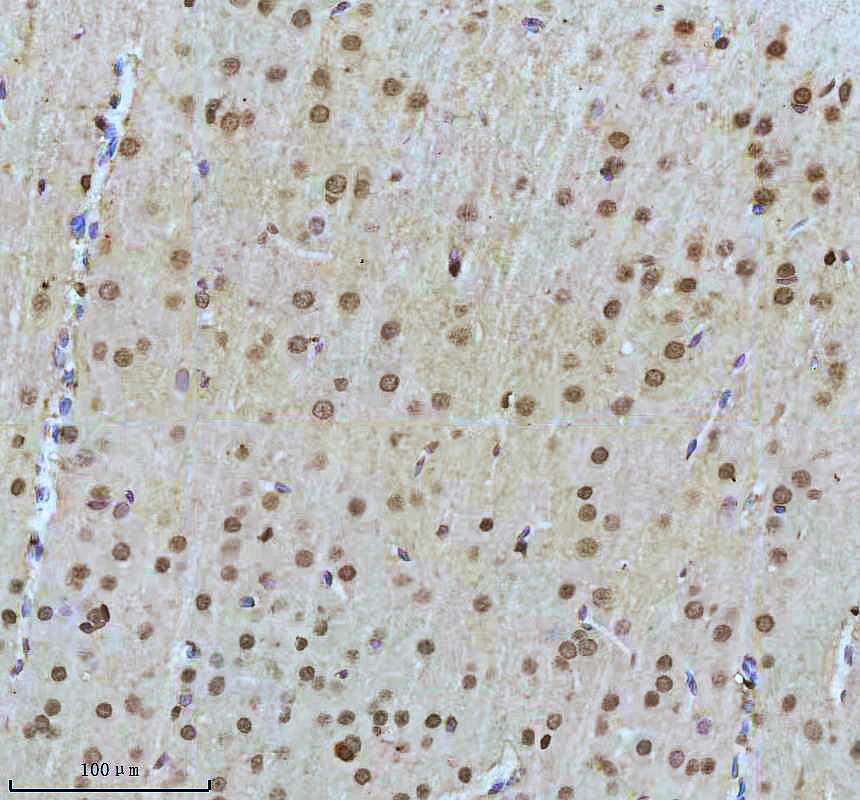

IHC analysis of SHP2/PTPN11 using anti-SHP2/PTPN11 antibody (BM4588) .

SHP2/PTPN11 was detected in a paraffin-embedded section of mouse brain tissue. The tissue section was incubated with rabbit anti-SHP2/PTPN11 Antibody (BM4588) at a dilution of 1:200 and developed using HRP Conjugated Rabbit IgG Super Vision Assay Kit (Catalog # SV0002) with DAB (Catalog # AR1027) as the chromogen.